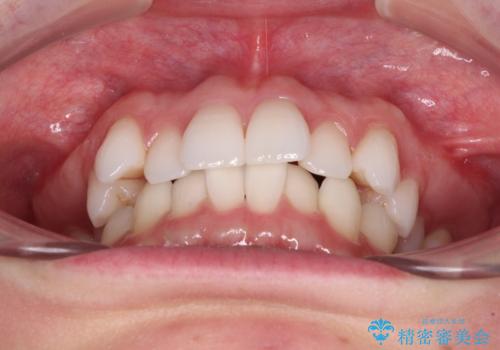

【モニター】インビザラインで気になるデコボコと八重歯をきれいに整える

- 上下前歯のデコボコ、特に右上の八重歯を気にして来院された患者様です。

妊娠、出産の予定があり、毎月の通院が困難となる可能性があったため、インビザラインによる矯正治療を行うこととしました。

事前に親知らずを抜歯しておき、出産時期に困ることのないように準備をした上で治療を開始しました。